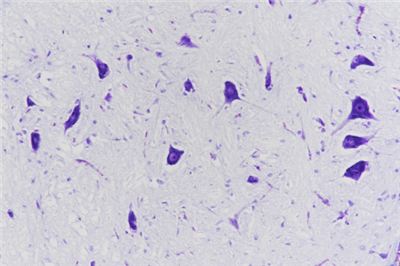

神经元细胞体包括一个具有皱褶核膜的大细胞核、稀疏的染色质和一个明显的核仁。在细胞体中细胞质是尼氏颗粒,即能够代表粗面内质网并在很多神经元中产生特异的斑点状嗜碱性表现的嗜碱性颗粒。尼氏颗粒可以用很多染色来显示如中性红、亚甲基蓝、甲苯胺蓝和甲基紫等。染色的变异、pH和分化的时间使一些染色既可以仅突出尼氏物质,也可以显示神经元的细胞核和神经胶质。各种神经细胞内都含有尼氏体,但其形状、数量、分布位置常常不同。尼氏体也存在于树突中,但不在于轴突和胞体的轴丘。尼氏体会因为生理状态的变化而变化,尼氏体是神经元内合成蛋白质合成的重要部位,当神经元受到刺激后,胞体内的尼氏体会明显减少。通常尼氏体能被碱性染料如硫堇、亚甲蓝、甲苯胺蓝和焦油紫等染料染成紫蓝色。

染色结果:尼氏体呈紫色、细胞核呈蓝色